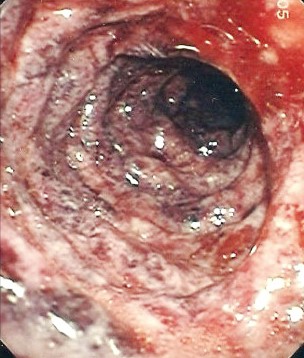

ЭГДС выявляет отечную, изъязвленную и некротическую слизистую постбульбарного отдела дуоденум с протеканием крови из этих мест, предполагающих гастроинтестинальную ишемию (рис. 4). Возможно сочетанное поражение антрума желудка.